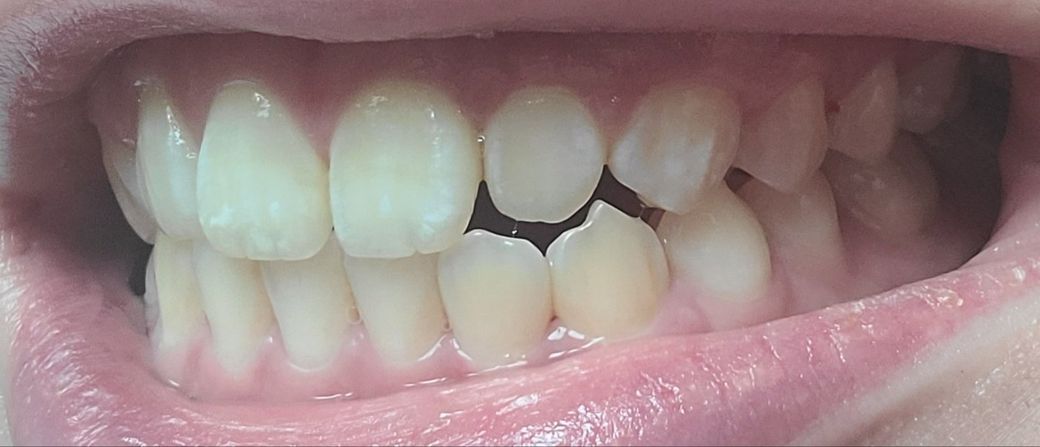

아래사진은 일부러 중심선맞춰서 찍은사진입니다

송곳니랑 그부근 어금니가 좀 더 틀어져서 깊게?물려요 턱이 비대칭이있긴한데 이정도비대칭은 사람마다 있다고들 하는데

-한쪽 송곳니은 살짝 떠있고 반대쪽은 잘물려요